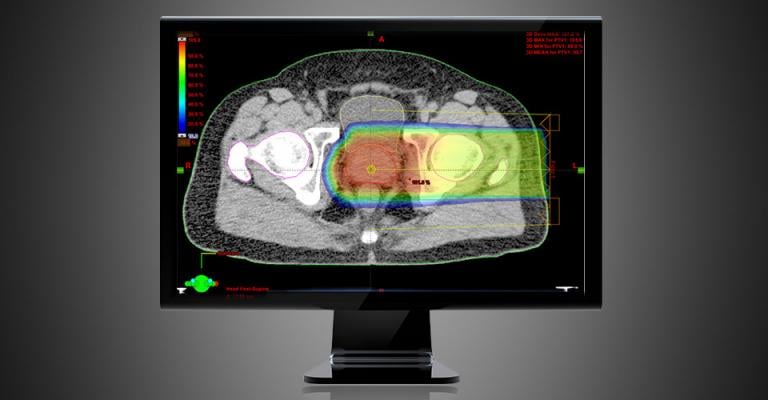

October 26, 2018 — During a recent users meeting, Varian shared details of its development work on an artificial intelligence (AI)-driven multimodality adaptive radiotherapy treatment suite being designed. The suite will deliver high-quality treatments and incorporates all types of imaging, including magnetic resonance imaging (MRI), positron emission tomography (PET) and computed tomography (CT).

During his presentation at the meeting, Ed Vertatschitsch, vice president of global portfolio solutions at Varian, outlined how the AI-driven multimodality suite is being designed to provide significant workflow improvements for clinicians and make it possible for a busy clinic to offer adaptive therapy to every patient that would benefit.

Vertatschitsch added the suite will use state-of-the-art treatment delivery, including 17-second high-resolution kV iterative cone beam CT (CBCT) imaging and Varian’s advanced multi-leaf collimator designed to enable delivery arcs that require just 30 seconds.

During his presentation, Vertatschitsch also discussed Varian's work to create a solution that offers an integrated workflow that makes it straightforward for the clinician to communicate the physician's intentions, adapt and monitor the patient treatments.